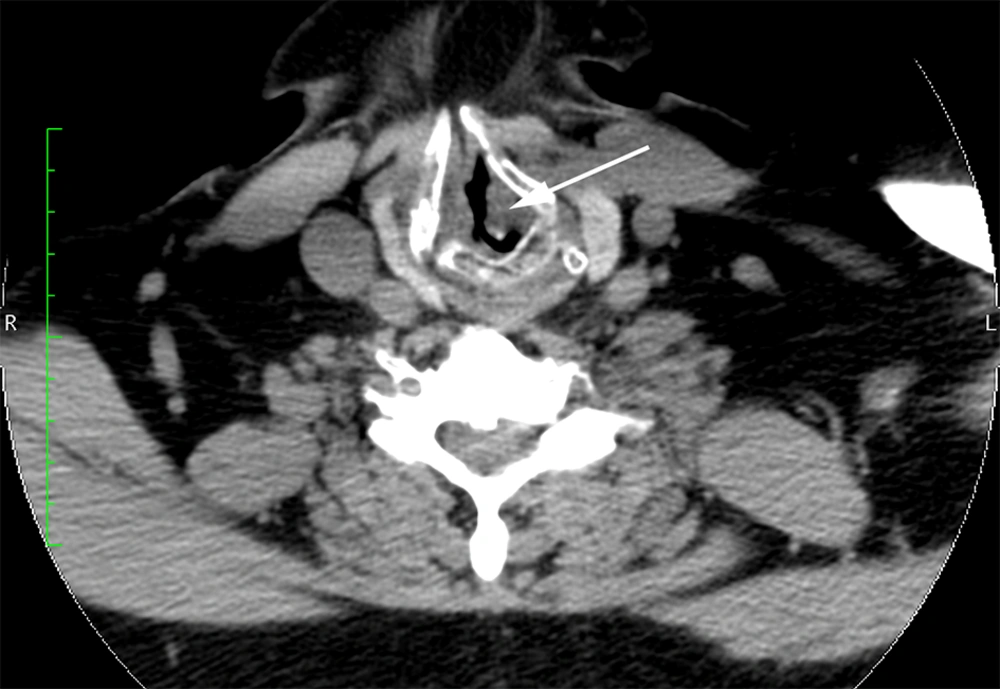

Because of the patient’s symptoms and the authors’ videoendoscopy findings, the patient was referred to the otolaryngology clinic for further evaluation. Computed tomography revealed tracheal stenosis; a segment of the proximal subglottic trachea was narrowed to a diameter of approximately 4 mm (Figure 2). Computed tomography also showed cartilageous erosion consistent with tracheomalacia. The otolaryngology consultant initially proposed tracheal reconstruction, but this option was not feasible in the short term because of the urgent need to address the infected knee arthroplasty. The otolaryngologist concurred with the authors who were concerned that repetitive endotracheal intubation and extubation was not an option for this patient with a substantially narrowed glottis and subglottic stenosis. As a result, the patient underwent an elective permanent tracheostomy under conscious sedation (intravenous midazolam and fentanyl) to obtain definitive control of his airway immediately before the infected knee arthroplasty was removed and antibiotic spacers were placed after induction of general anesthesia. A subsequent incision and drainage procedure was also performed. The patient eventually underwent a revision total knee arthroplasty several months later after the infection had been successfully treated. The patient made an uneventful recovery after each operation.

The authors’ examination of the current patient demonstrated several important new findings, including a narrowed glottis, supraglottic scarring, subglottic stenosis, and redundant lower oropharyngeal tissue, suggesting that his airway may be difficult to repeatedly secure using conventional methods for his orthopedic surgery procedures. These observations, along with the computed tomography results, also indicated the possibility that proximal tracheal injury may occur with endotracheal intubation or that edema may compromise the patency of an already narrowed airway when the endotracheal tube was removed. As a result, the patient underwent an elective permanent tracheostomy to establish a definite airway for the anticipated operations required for treatment of his infected total knee arthroplasty. The authors did briefly consider performing a series of neuraxial anesthetics for the patient’s anticipated operations, but this option was dismissed because the patient had a long standing infection with the possibility of bacteremia despite chronic antibiotic therapy and also had a history of symptomatic lumbar spinal stenosis. The authors were also concerned that inadequate neuraxial or regional anesthesia during surgery may necessitate urgent airway intervention in this patient with significant airway abnormalities.